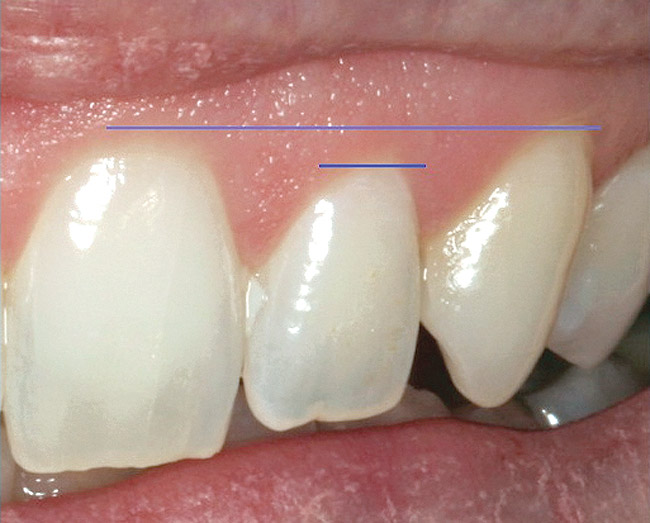

Gingival Margin Location/Symmetry

Will the removal or retention of the tooth allow gingival symmetry? Gingival symmetry is defined as an imaginary line that should be collinear, connecting the central incisors and canines and parallel with the interpupillary line or horizon if the interpupillary line is canted. Ideally, this line should also be parallel to the incisal edge and the curvature of the lower lip.37 The gingival margin of the lateral incisor should be even with or coronal to this line by a maximum of 3 mm (Figure 16).38 If these parameters are not met, then orthodontic or periodontal procedures or both will need to be performed to place the tooth in the correct esthetic position.

Figure 16  ENDODONTIC AND ESTHETIC PARAMETERS  Gingival symmetry is defined as an imaginary line that should be collinear connecting the central incisors and canines. The gingival margin of the lateral incisor should be even with or coronal to this line by a maximum of 3 mm.

Figure 16